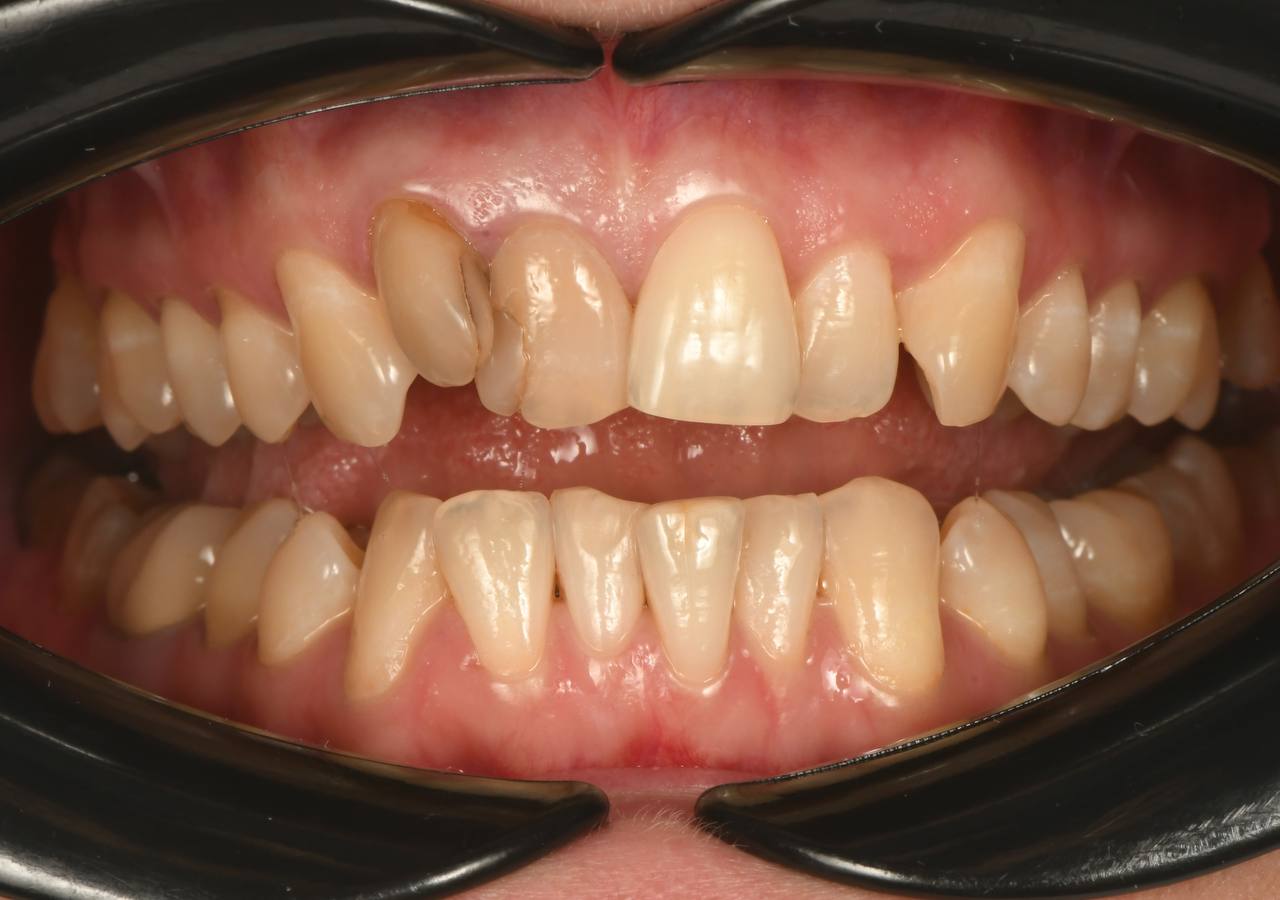

Непростая ситуация, связанная с расположением зубов: лечение кариеса до начала ортодонтического лечения проведено максимально эффективно. Профессионалы своего дела!

Меня беспокила стираемость зубов и после диагностики высянилось,что мне необходимо комбинированное ортодонтическое лечение совместно с челюстно-лицевым хирургом. Результат поразил всех близких - изменения по профилю были настолько заметны, что пришлось и

Сложность моего случая даже фото не отображает , как мне кажется. Комплексный подход ортодонта,хирурга и ортопеда в клинике ОК показал,что невозможное возможно!! Главное обратиться в специализированную клинику!! Благодарю всю команду океян!